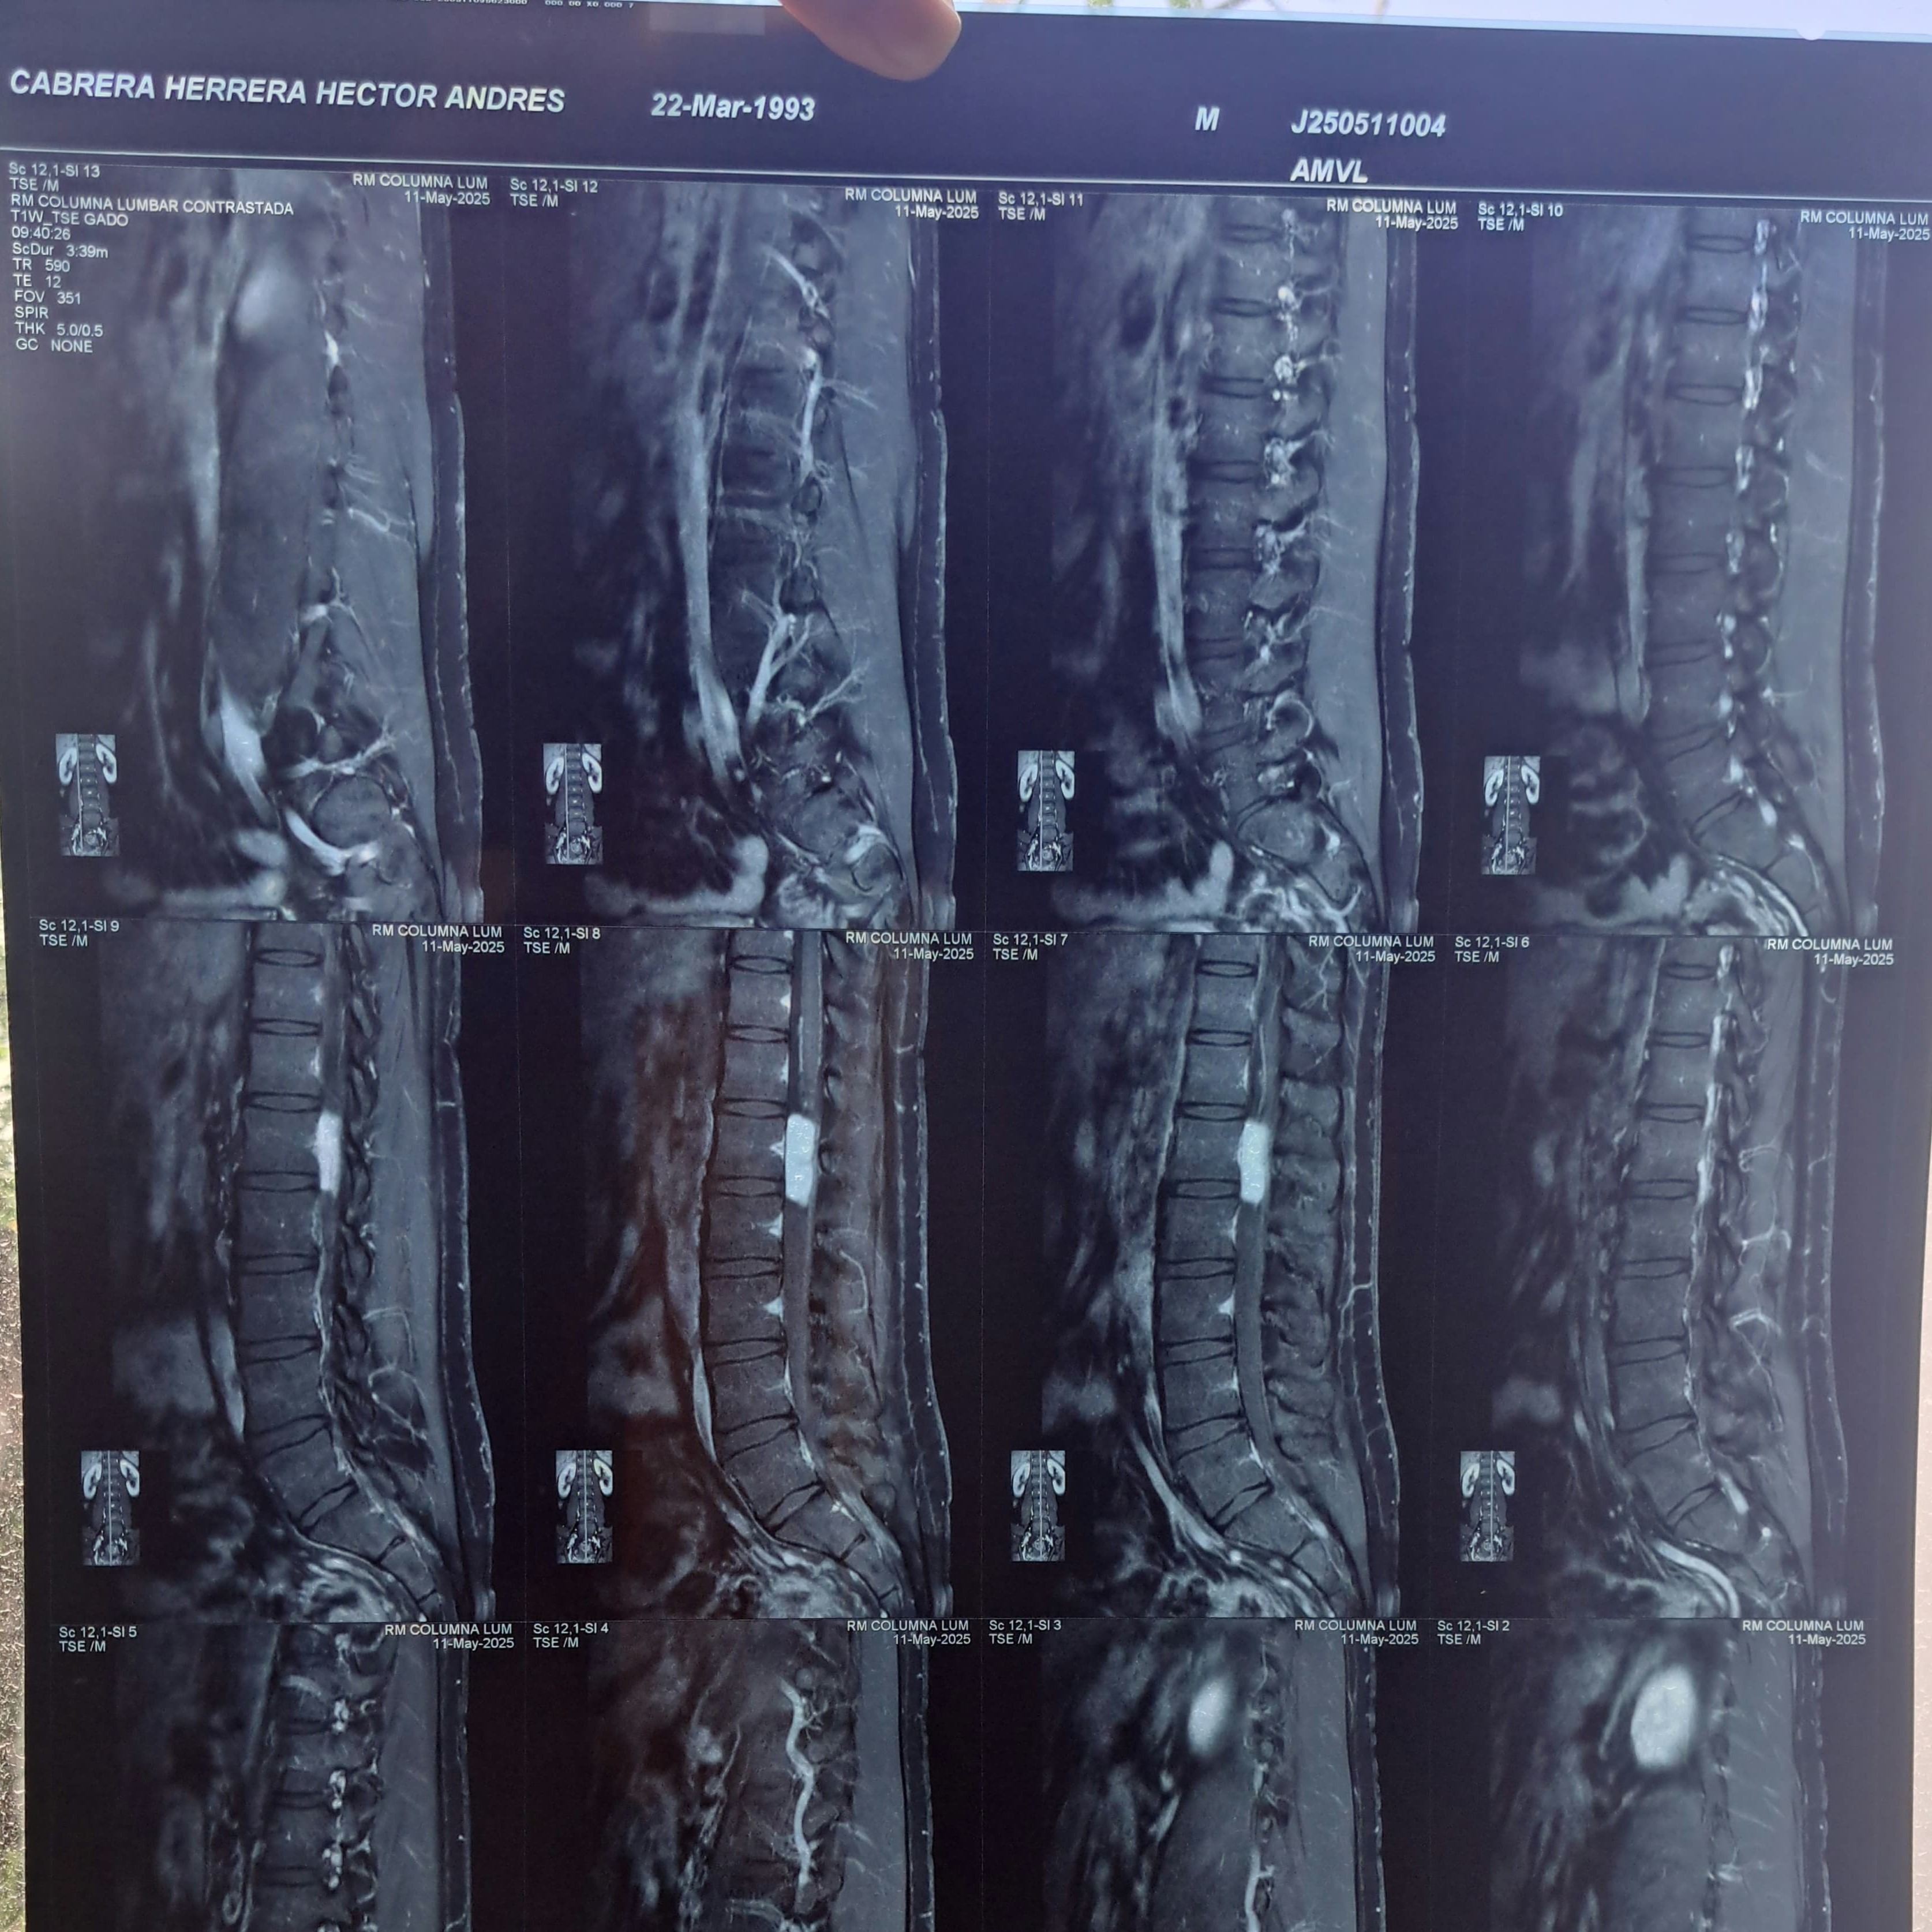

Comencé con un dolor en la zona lumbar a finales de febrero de 2025 y todo parecía indicar que era la ciática, según el traumatólogo. Empecé con fisioterapia, pero el dolor iba en aumento mientras pasaban las semanas y ya nada me lo controlaba. Mi calidad de sueño y de vida se vio afectada, por lo que me sugirieron me realizara una resonancia magnética.

En cuanto se recibió el resultado de dicho estudio el día 7 de mayo de 2025 me detectaron un tumor en la médula espinal en la zona lumbar, el cual por el tamaño y ubicación se tiene que remover con cirugía indiscutible y urgentemente. El tumor ocupa el diámetro del conducto de la médula espinal en la zona L1 y de momento está encapsulado. El no realizarme la cirugía implicaría de inicio la pérdida progresiva y definitiva de la movilidad y sensibilidad en ambas piernas, así como del control de esfínteres. Hasta no haber extirpado el tumor y tener el análisis de patología se sabrá exactamente de qué tipo es.

I began experiencing pain in my lower back at the end of February 2025, and everything seemed to indicate sciatica, according to the orthopedic surgeon. I started physical therapy, but the pain increased as the weeks went by, and nothing was controlling it. My quality of sleep and life were affected, so they suggested I get an MRI.

As soon as the results of the study were received on May 7, 2025, they detected a tumor in my spinal cord in the lumbar region. Due to its size and location, it must be removed urgently and unquestionably by surgery. The tumor occupies the diameter of the spinal cord canal in the L1 region and is currently encapsulated. Not undergoing surgery would initially imply the progressive and permanent loss of mobility and sensation in both legs, as well as sphincter control. Until the tumor is removed and the pathology analysis is completed, the exact type will be known.